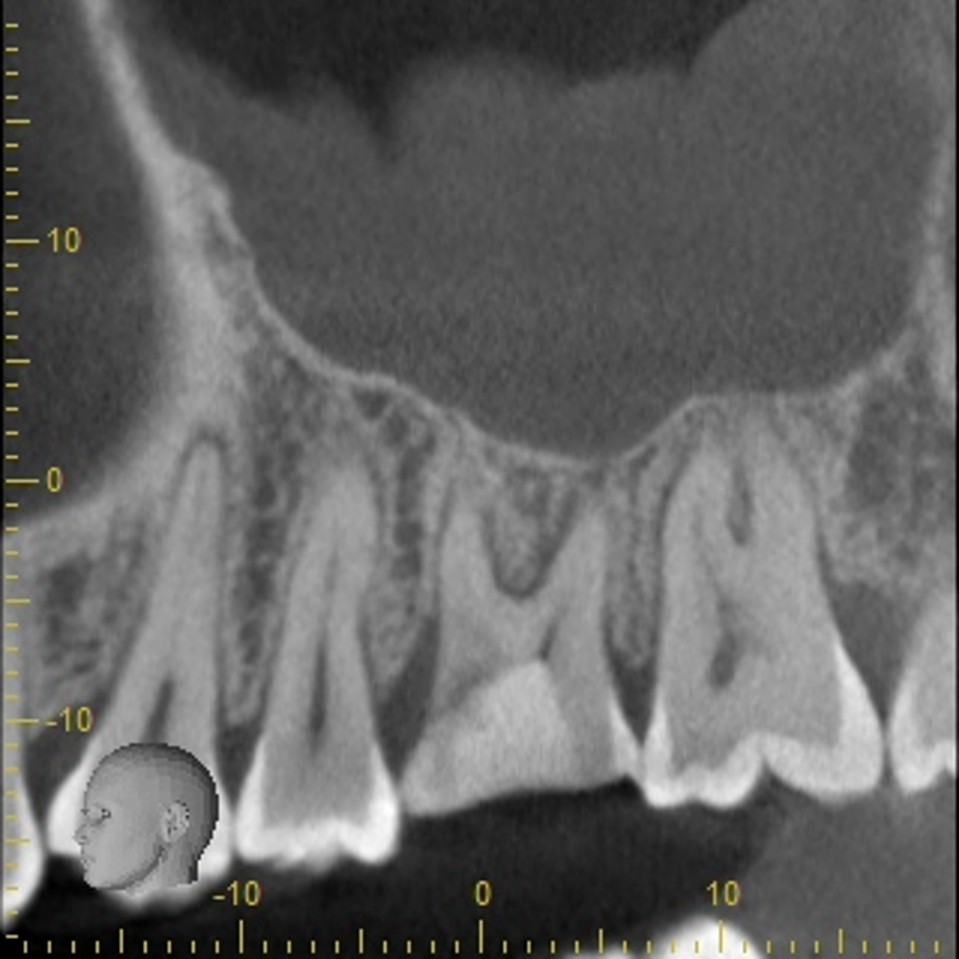

このように健康な歯が真っ二つに割れることはめったにないのですが、こうなると神経に触る様な強い痛みが出ますし、CTスキャンをとると上顎洞炎にもなっていました。

上の奥歯は上顎洞までの距離が短くインプラントが難しいことも多いのですが、即時埋入用に開発されたインプラントを使えば抜歯と同時にインプラント埋め込みまで行うことができると判断しました。

CTスキャンで確認してみても上顎洞炎もきれいに治っていることが分かります。